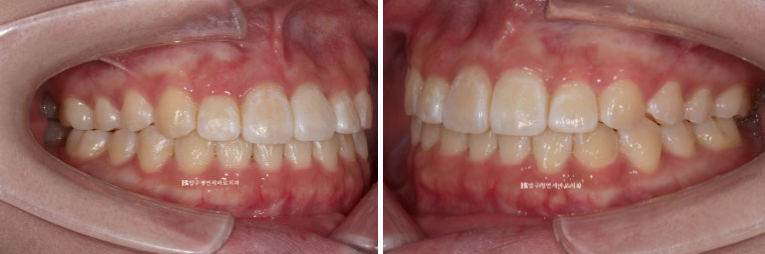

24.01

들려있던 일자로 내려오면서 치아가 처음보다 약간 길어보입니다.

23.04~24.01

앞니 각도 전 후 변화입니다.

웃을 때 치아가 일자로 딱 떨어지는 모양새가 보기에 가장 좋습니다.

앞니가 상당량 후방이동 하며 입술도 뒤로 들어갔습니다.